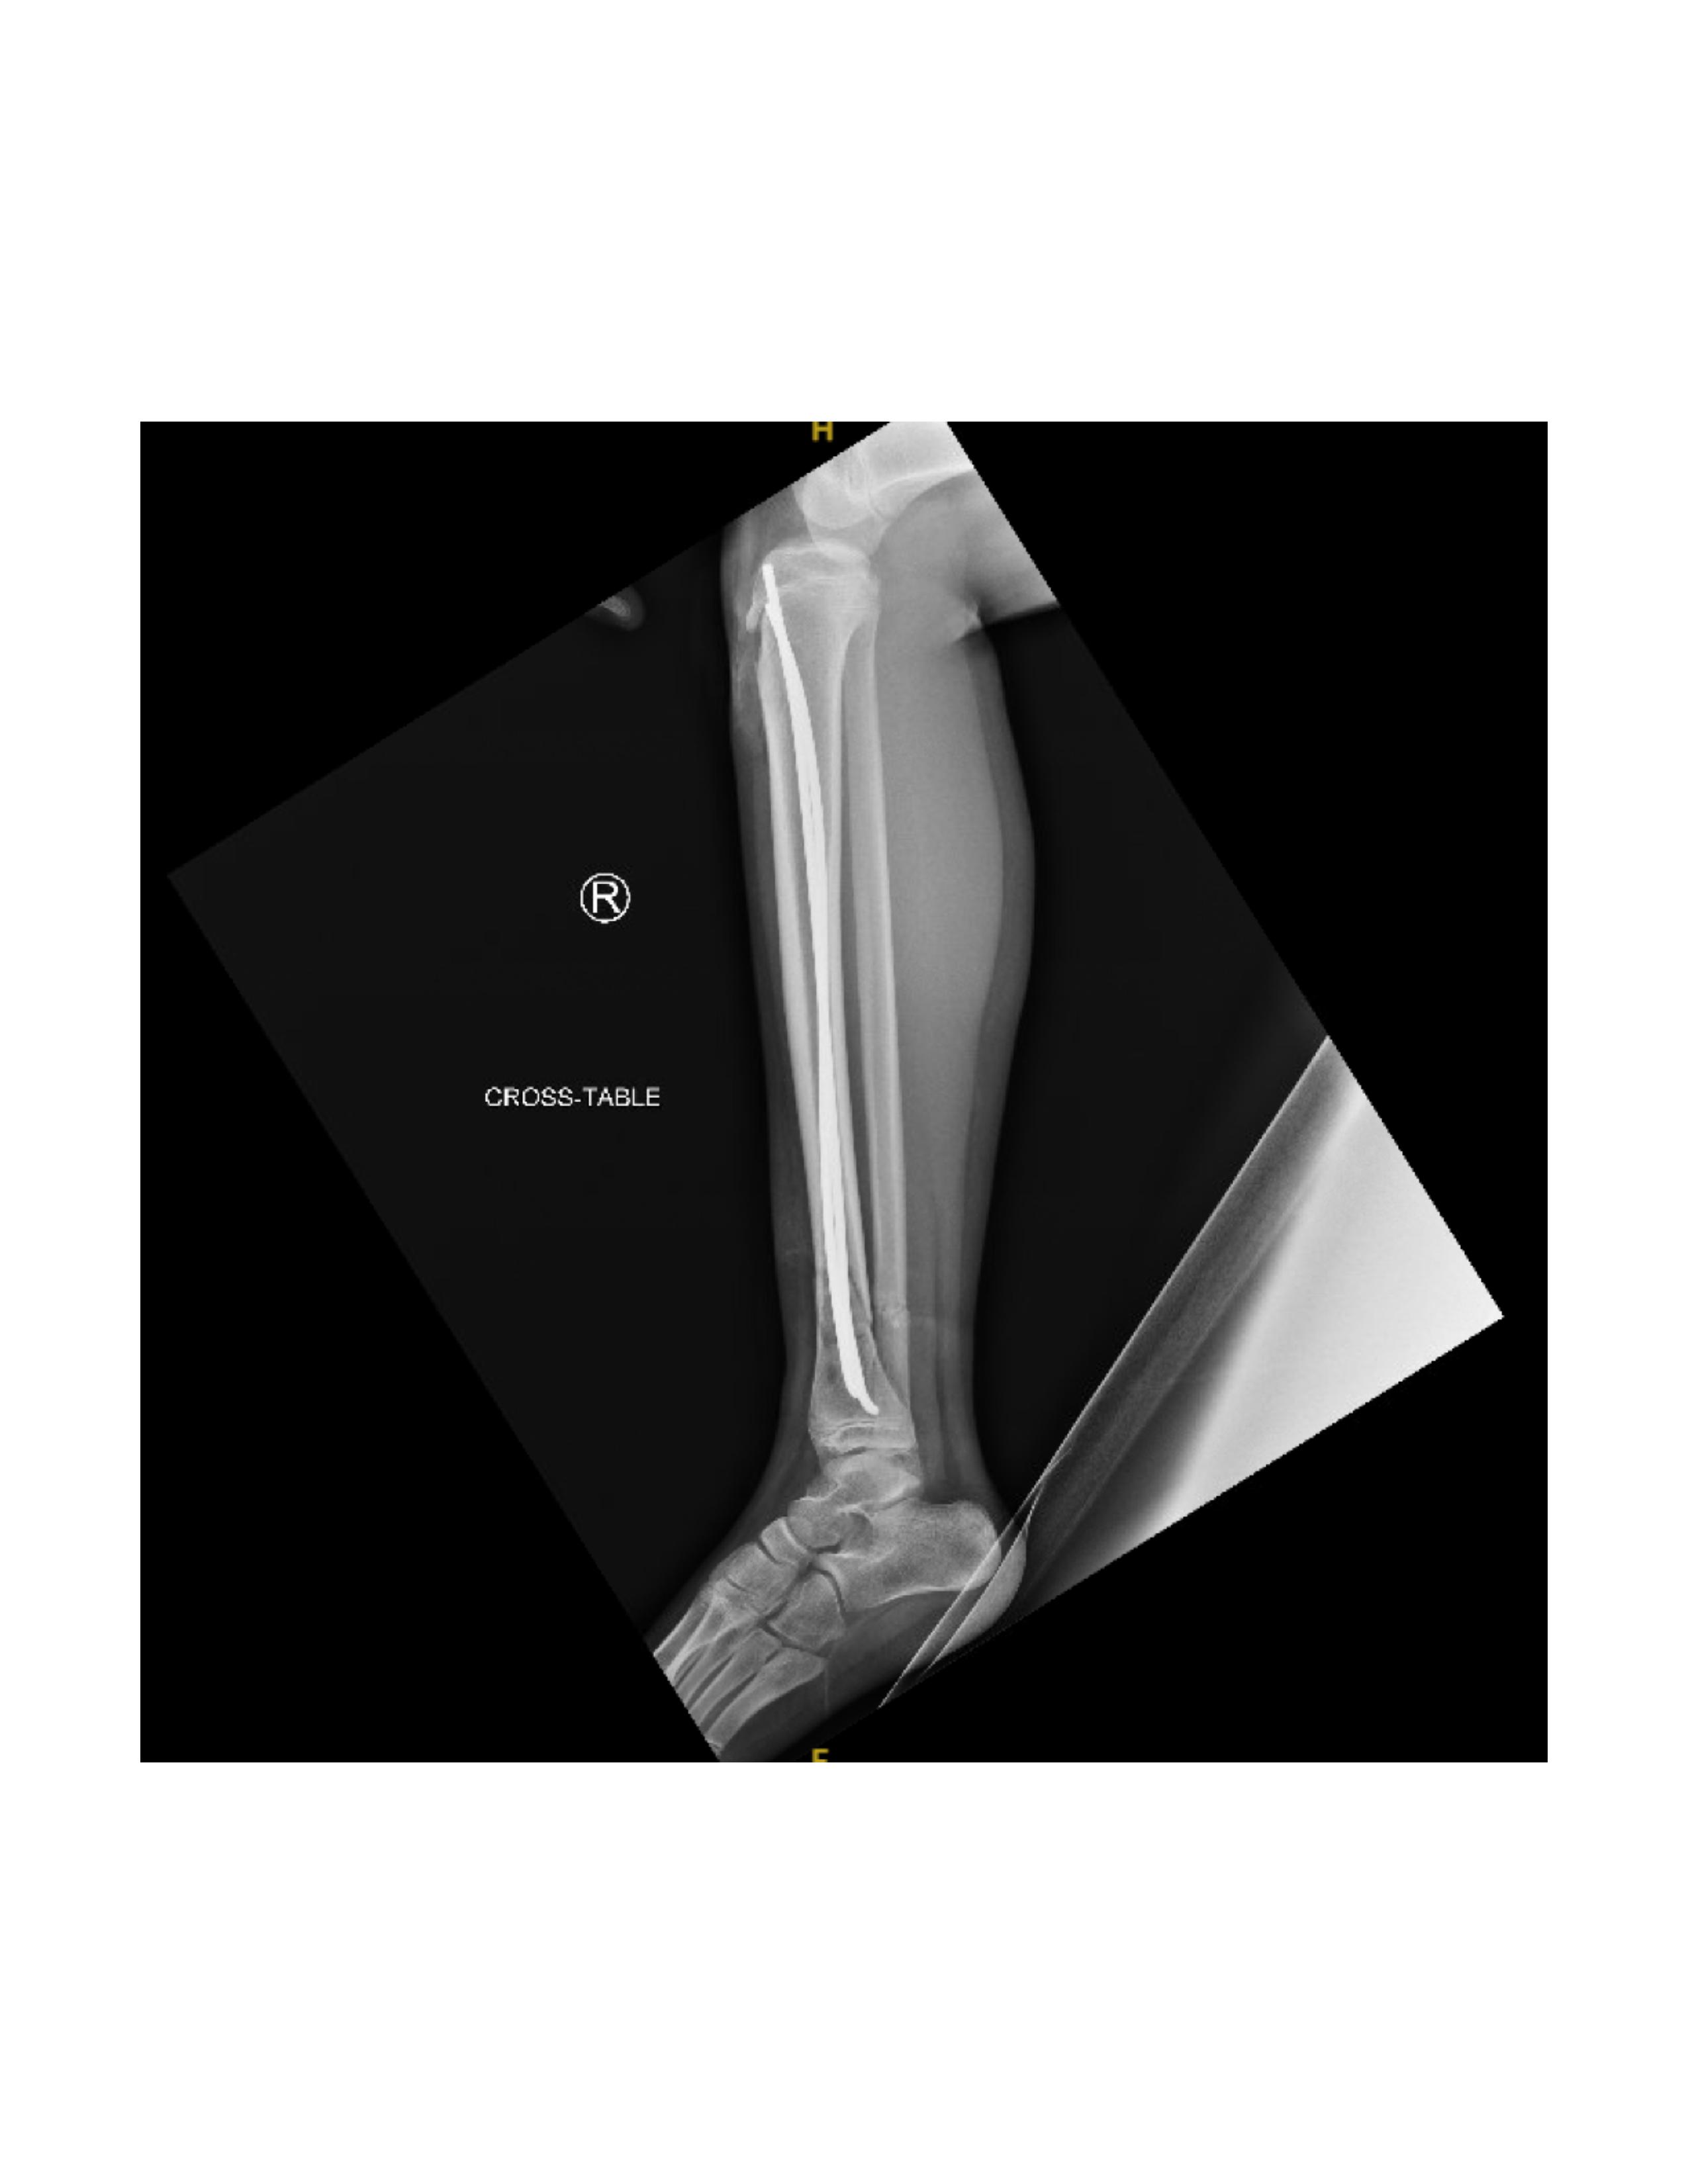

Next, the fracture is manually reduced and both nails are gently advanced past the fracture site by mallet. The curvature of the nails and their tips assists in reducing and stabilizing the fracture, inserted shy of the growth plate. Nail positioning is confirmed by fluoroscopy (Figure 5).

The fracture site is then reassessed under fluoroscopy to confirm maintained reduction. (Figure 8 and Figure 9) Wounds are irrigated and closed in two layers, followed by sterile dressing and short leg splint application.